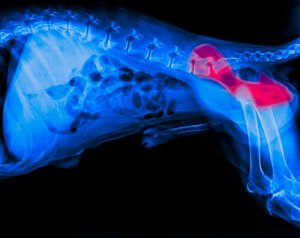

Es handelt sich um eine Krankheit, die den Hüftbereich und seine Gelenke betrifft. Sie wird durch die fehlerhafte Verbindung des Hüftgelenkkopfes mit dem entsprechenden Hohlraum in der Hüfte verursacht.

Wenn dies der Fall ist, baut sich das Gewebe ab, der Hund fühlt sich beim Gehen unwohl und beginnt zu lahmen.

Wenn du eines dieser Symptome beobachtest, solltest du deinen Hund zum Tierarzt bringen, wo man bestimmt eine Röntgenaufnahme macht, um die Krankheit zu bestätigen.